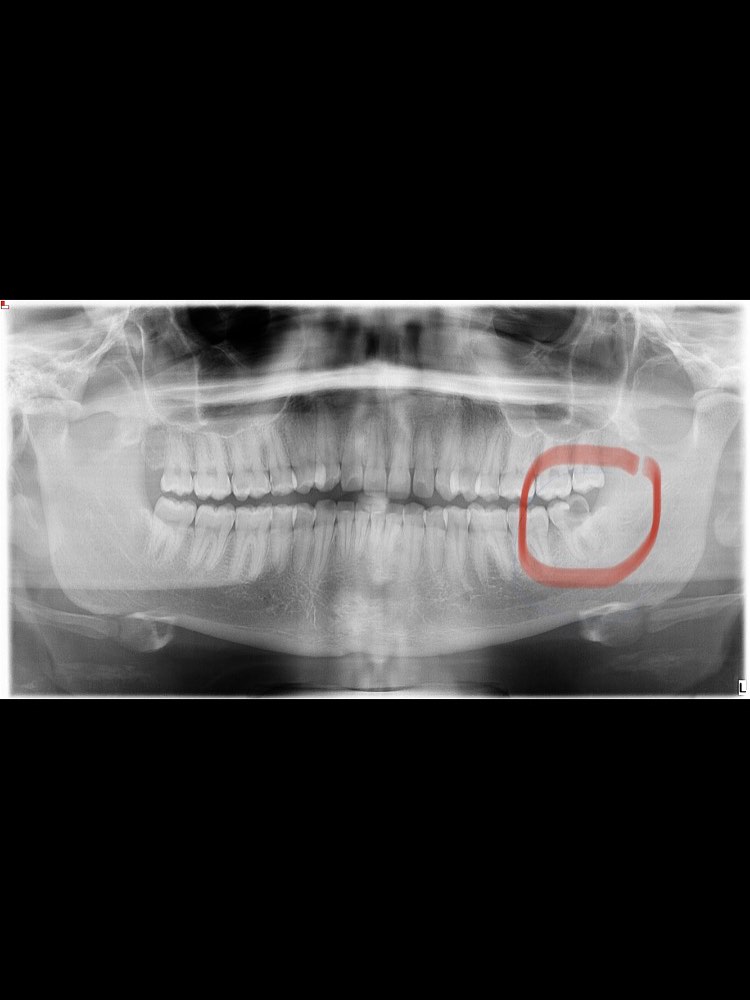

Explore Our Clinical Dental Gallery

Welcome to our official treatment gallery, showcasing the real results, smile transformations, and advanced dental care delivered by Dr. Madhuri. We believe that a picture is worth a thousand words when it comes to the art and precision of modern dentistry. Review our comprehensive visual portfolio below to see how our dedicated care helps patients achieve healthy, beautiful, and confident smiles.